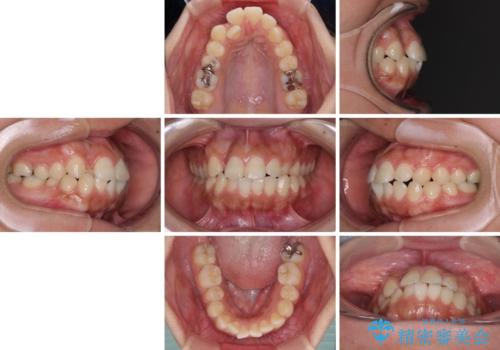

- 口元の突出感を気にして来院された患者様です。

デコボコと口元の突出感が認められたため、上下左右の第1小臼歯4本を抜歯してのワイヤー矯正を行うこととしました。

上顎歯列の横幅が狭く、下顎大臼歯の歯軸が舌側に倒れていたため、急速拡大装置により上顎骨を側方に拡大し、咬み合わせを改善することとしました。

上顎歯列幅を拡大したことで、デコボコを容易に解消することができるようになったため、抜歯により得られたスペースを口元の突出感改善に利用することができました。